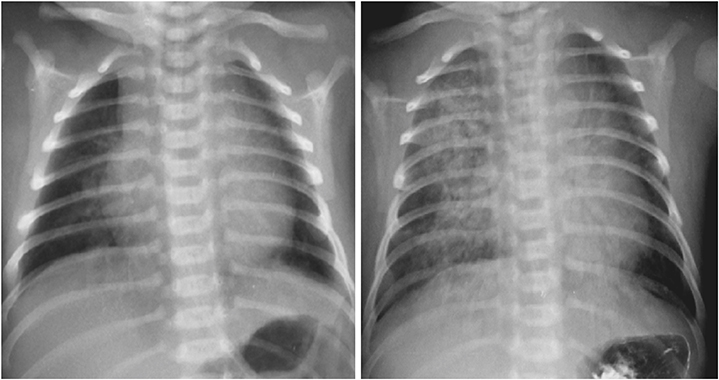

A male full-term neonate presented to emergency room with cyanosis after breastfeeding. The patient was delivered by planned caesarian section 12 hours before arrival. Chest radiograph taken on the first day of life was cleaned but the radiograph taken on the third day of life suggested aspiration pneumonitis (

Fig. 1 Two days after birth (right), chest radiograph shows aspiration pneumonitis which was absent on the date of birth (left).